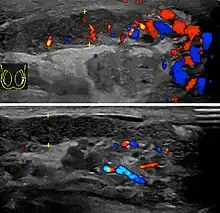

Epididymitis usually has a gradual onset. Typical findings are redness, warmth, and swelling of the scrotum, with tenderness behind the testicle, away from the middle (this is the normal position of the epididymis relative to the testicle). The cremasteric reflex (elevation of the testicle in response to stroking the upper inner thigh) remains normal.[1] This is a useful sign to distinguish it from testicular torsion. If there is pain relieved by elevation of the testicle, this is called Prehn's sign, which is, however, non-specific and is not useful for diagnosis.[13] Before the advent of sophisticated medical imaging techniques, surgical exploration was the standard of care. Today, Doppler ultrasound is a common test: it can demonstrate areas of blood flow and can distinguish clearly between epididymitis and torsion. However, as torsion and other sources of testicular pain can often be determined by palpation alone, some studies have suggested that the only real benefit of an ultrasound is to assure the person that they do not have testicular cancer.[14]: p.237 Nuclear testicular blood flow testing is rarely used.